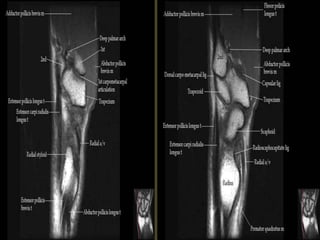

The transverse carpal ligament (short arrows) extends from the hook of the hamate (long

arrow) to the tubercle of the trapezium (arrowhead), forming the floor of the carpal tunnel.

At the radial aspect of the carpal tunnel, the flexor digitorum tendons are arranged in two

rows (separated by dotted line), the profundus tendons deep to the superficialis tendons. The

flexor pollicis longus tendon (star) is positioned at the ulnar aspect of the tunnel, separated

from the flexor carpi radialis tendon (curved arrow) by a ligamentous reflection of the

transverse carpal ligament. The median nerve is indicated (asterisk). - See more at:

http://radsource.us/palmar-bursae-and-flexor-tendon-sheaths/#sthash.mSFX1u0c.dpuf